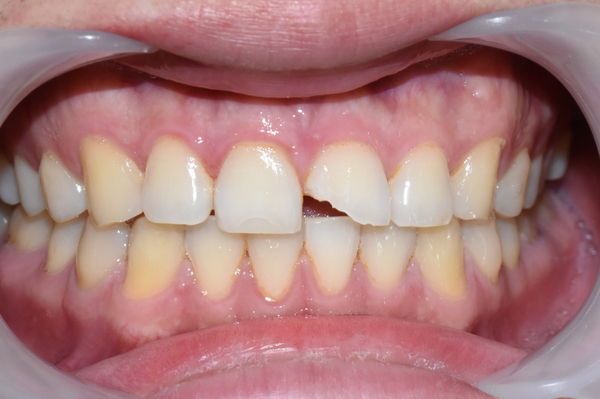

위 환자분은 "술먹고 넘어져서 앞니가 깨졌다"라는 내용으로 내원하였습니다.

위 앞니 2개 중에 1개(사진상 오른쪽)는 굉장히 많이 사선 방향으로 깨졌고

다른 1개(사진상 왼쪽)은 사진에서도 보이듯이 금이 가있는 상태였습니다.

부딪혀서 깨진 앞니. 앞니 뒤에 붙어있던 교정 유지장치

씹을 떄 건드릴 때 아픈 상태였고 많이 깨진 치아는 시리기도 했습니다.